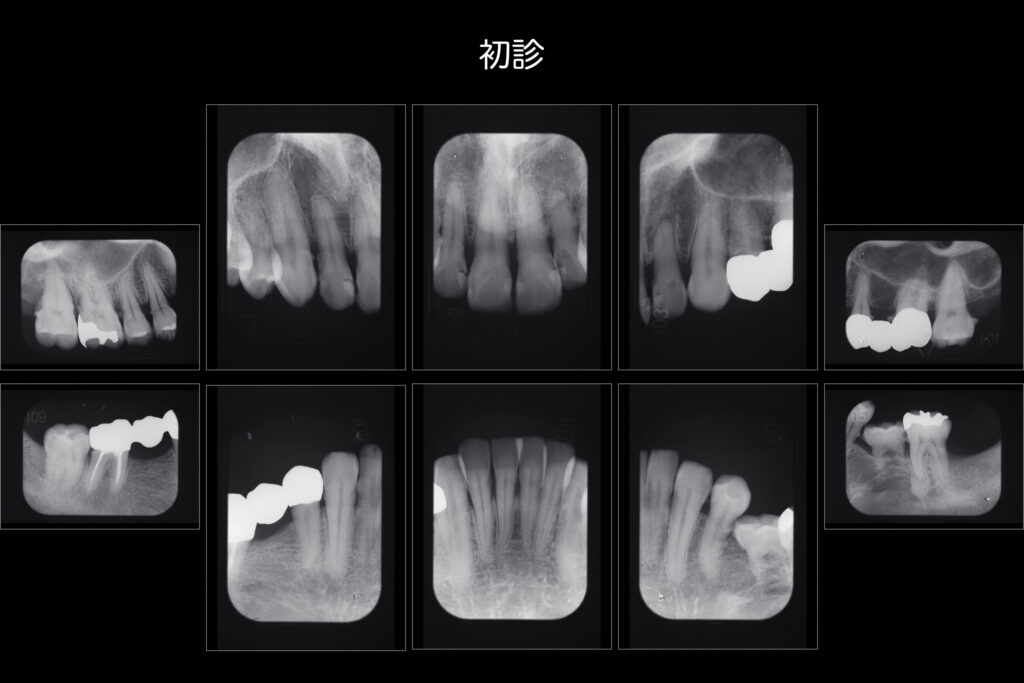

先日は就業時間内に時間を取りより患者様へ寄り添った歯科診療を行えるよう月一回の院内勉強会を行いました。

演者は歯科衛生士Sさんによる歯周基本治療の成果や経過の臨床発表でした。

歯周外科(歯ぐきを切って外科的に歯石を取ったりすること)を行わず、患者様と2人3脚で改善している様は

担当衛生士S(全力サポート衛生士N)はもちろん患者様自身のセルフケアの劇的向上によるものです。

今後もより良い経過が続くよう寄り添って参ります。

できる限り自分の歯で人生を楽しみたい方は是非ご相談ください。